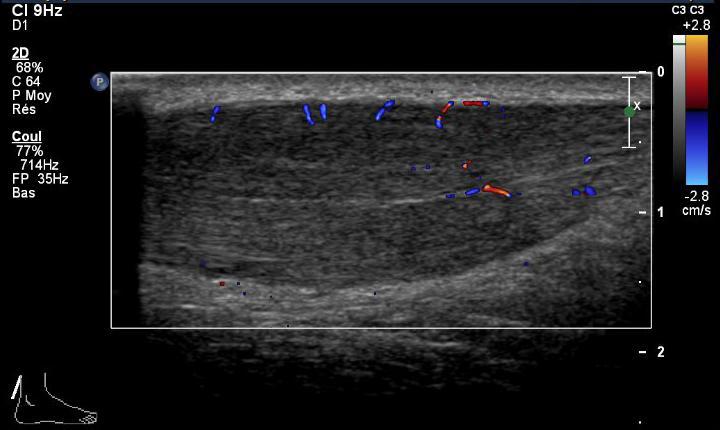

Ce traitement consiste en l’injection d’un volume important de NaCl 0,9% en péritendineux (40 ml), après avoir effectué une anesthésie locale de 5ml de Bupivacaïne 0,5%.

Fig.1 Aiguille en contact avec le tendon achille

Fig.2 Remplissage du péritendon de 40 ml de NaCl 0.9%

Fig.3 AVANT traitement

Fig.4 APRES traitement

Après l’injection, le mollet est bandé et un repos de 48 heures est nécessaire. Dès le 3ème jour, un traitement de physiothérapie est initié. Un traitement antioxydant per os (1 gr de vit.C / j.) pendant 2 mois est prescrit après l'infiltration.